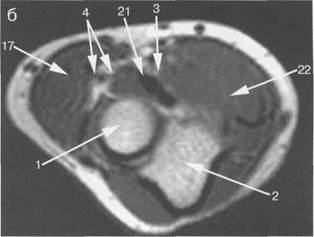

Рис. 19.33. МРТ локтевого сустава. Аксиальная плоскость.

а: 4 — m. brachialis; 8 — медиальный надмыщелок; 10 — лок­тевой отросток локтевой кости; 17 — m. brachioradialis; 19 — т. anconeus; 20 — nervusulnaris; 21 — сухожи­лие т. biceps brachii; 22 — т. pronator teres.

б: 1 — головка лучевой кости; 2 — локтевая кость; 3 — п. medianus; 4 — arteria, vena, п. radialis; 17 — m. brachioradialis; 21 — сухожилие m. biceps brachii; 22 — m. pronator teres.